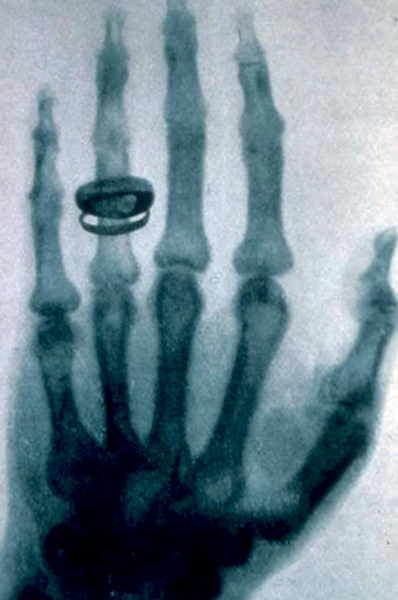

Hasta hace poco más de cien años, la única forma de ver el interior del cuerpo humano era abriéndolo. Todo comenzó a cambiar en diciembre de 1895 cuando el físico alemán Wilhelm Conrad Röntgen, intrigado porque al poner en marcha un tubo catódico en una esquina de su laboratorio se iluminaba un bote de sales de bario que tenía en la otra punta pese a que entre ambos objetos tenía gran cantidad de libros, pidió a su mujer, Ana Bertha, que pusiera la mano entre el tubo catódico y una placa fotográfica, logrando así la primera y más conocida radiografía de la historia: la mano de su mujer.

Descubrimiento casual. La mano de Ana Berta, esposa del físico alemán Wilhelm Conrad Röntgen, fue la primera y más conocida radiografía de la historia. Se trató de un hallazgo casual, ya que el científico quería comprobar por qué un tubo catódico iluminaba un bote de sales de bario situado en la otra punta de su laboratorio, para lo que solicitó a su mujer que pusiese en medio su mano. Era un día de noviembre de 1895 y se acababan de descubrir los rayos X.